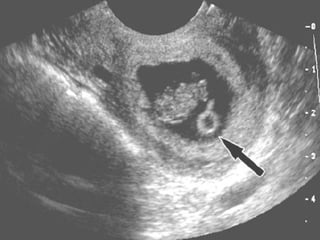

ECOGRAFIA El diagnóstico del EE se ha beneficiado de los avances producidos en el campo de la ecografía, principalmente a través del desarrollo de la vía transvaginal. Varios son los hallazgos ecográficos sugestivos o diagnósticos de EE: - Ausencia de saco intrauterino: un título de b-HCG superior a 1000-1500 UI/l sin saco intrauterino es compatible con EE. Con gestaciones múltiples, el saco gestacional no es visible hasta que los títulos son ligeramente mayores. Por otra parte, la comprobación de un embarazo intrauterino viable no permite descartar por completo la existencia de un EE, debiendo descartar un embarazo heterotópico especialmente cuando se han empleado técnicas de reproducción asistida.

-  Masa anexial anormal que puede  presentarse ecográficamente de diferentes formas: § Saco gestacional típico: corona ecogénica que delimita centralmente una laguna anecoica. § Actividad cardiaca anexial factible cuando los niveles de b-HCG son de aproximadamente 15000-20000 U/l. § Hematosalpinx, aisladamente o asociado al saco gestacional. § Hemoperitoneo, infrecuente cuando el diagnóstico se establece de forma precoz.

¿Que tipo de ecografía?  La ecografía  transvaginal antecede en una semana a la ecografía abdominal en la detección de una gestación intrauterina. La ecografía  transvaginal detecta las masas anexiales mejor que la ecografía abdominal.

Saco seudogestacional  de embarazo ectópico y embarazo temprano intrauterino normal (EIU)